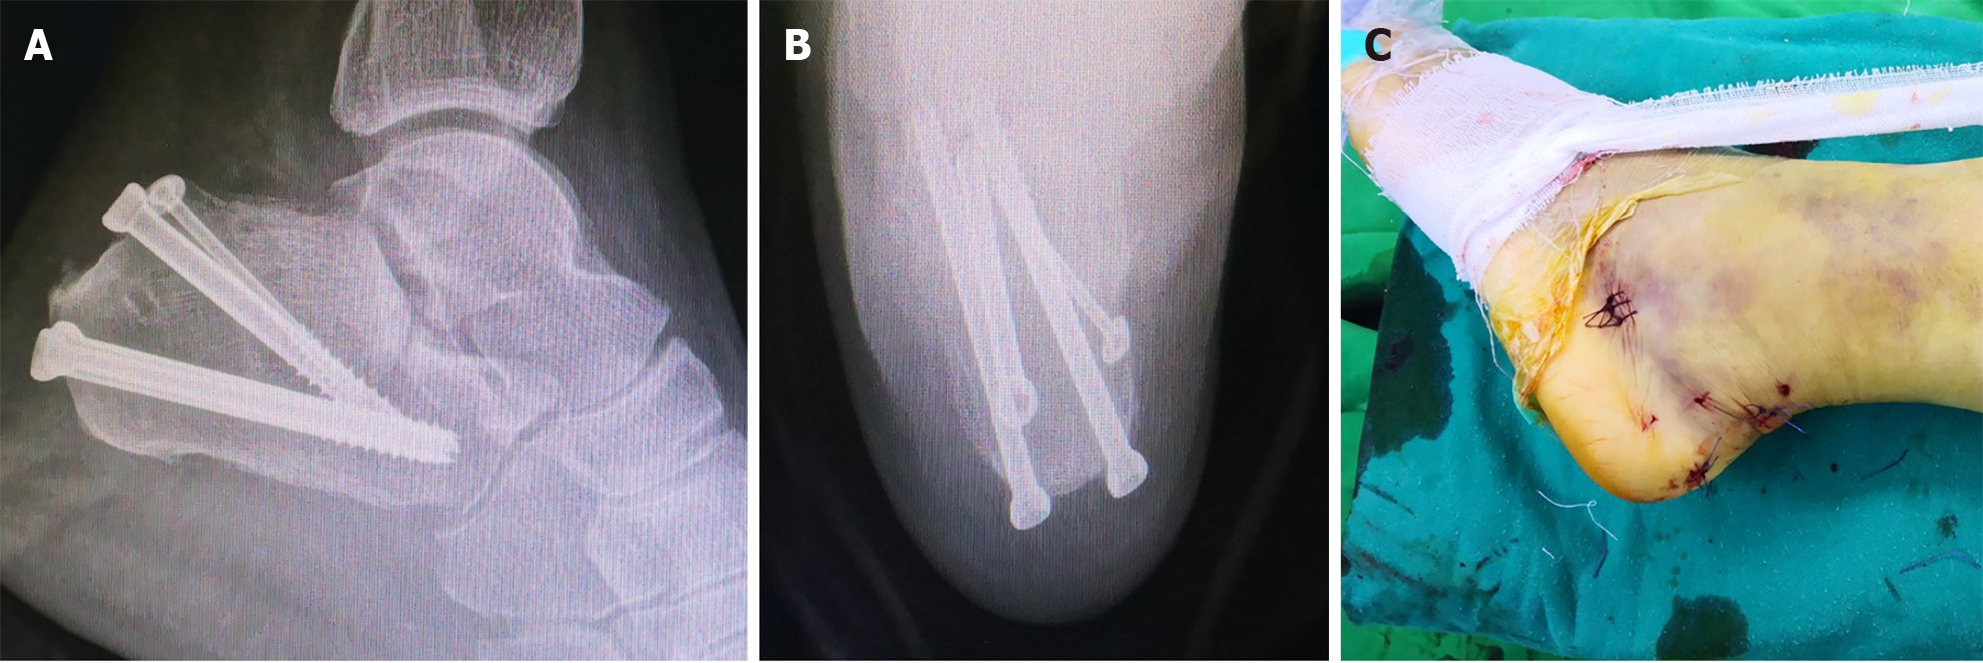

Figure 5 Surgical incision and intraoperative fixation.

A and B: Fluoroscopic lateral (A) and axial (B) views demonstrating percutaneous screw fixation of the calcaneus; C: Photograph of the minimally invasive surgical incision.